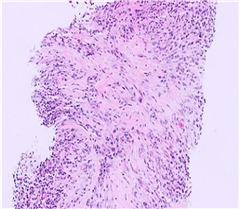

| 花むしろ様線維症(Storiform Fibrosis) |

リンパ形質細胞性炎症が散在する紡錘体細胞とコラーゲン束の花むしろ様配置。このパターンでは、線維化組織は、側転のスポークに似た、炎症病巣の周囲に放射状に広がる渦巻き状または渦巻き状に配置されます。この独特の線維構造は、この疾患の特徴として広く見なされており、その組織学的認識に大きく貢献しています。 (HE染色、×100) |